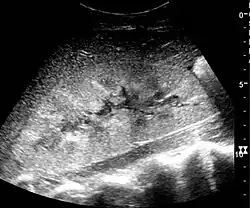

The diagnosis of AKI is made based on a person's signs and symptoms, along with lab tests for serum creatinine and measurement of urine output. Other tests include urine microscopy and urine electrolytes. Renal ultrasound can be obtained when a postrenal cause is suspected. A kidney biopsy may be obtained when intrinsic renal AKI is suspected and the cause is unclear.[5]

In medical imaging, the acute changes in the kidney are often examined with renal ultrasonography as the first-line modality, where CT scan and magnetic resonance imaging (MRI) are used for the follow-up examinations and when US fails to demonstrate abnormalities. In evaluation of the acute changes in the kidney, the echogenicity of the renal structures, the delineation of the kidney, the renal vascularity, kidney size and focal abnormalities are observed.[20] CT is preferred in renal traumas, but US is used for follow-up, especially in the patients suspected for the formation of urinomas. A CT scan of the abdomen will also demonstrate bladder distension or hydronephrosis.[21]